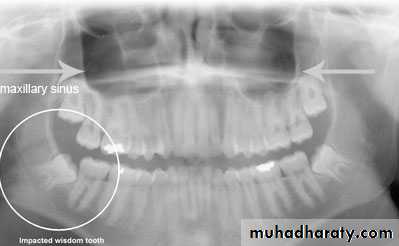

1- clinical inspection to disclose the missing tooth2- radiographic assessment showing the position of the unerupted tooth

c – panoramic view (OPG)

can be used to assess maxillary canine positiond – CT scan if necessary